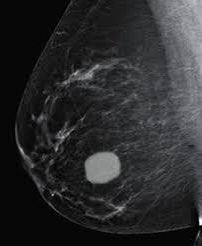

٢-التصوير الشعاعي للثديين

والذي يؤكد على وجود الورم ونوعه الحميد أو المشتبه به ويكون إما بالاشعه الصوتيه للنساء دون ٣٠عاما أو بالماموغرام والصوتيه لل ٣٠عاما وأكبر

8️⃣يميز الفحص الشعاعي بين التكتلات الصلبه والسائلة والتي تدعى بالاكياس وايضا صفاتها التي تشير الى كتلة حميده غير مقلقة أو الى كتلة فيها اشتباه تستدعي إجراء الخزعة

🔟-كيس الثدي البسيط

مملوء بالسوائل يتطور عادة في الثلاثينيات والأربعينيات من العمر. قد تظهر فجأة و تسبب ألامًا شديده تضطر الطبيب الى سحب وتصريف السوائل لتخفيف الالم

2️⃣2️⃣ سادسا: الالتزام بالكشف المبكر الدوري بالماموغرام للاعمار(٤٠-٦٩) ونعني بالمبكر أي اكتشاف المرض قبل تحوله للمرحلة الغازيه او في مراحلة قبل السريريه، وهنا يكون العلاج بسيط والشفاء تام قد يصل ١٠٠٪